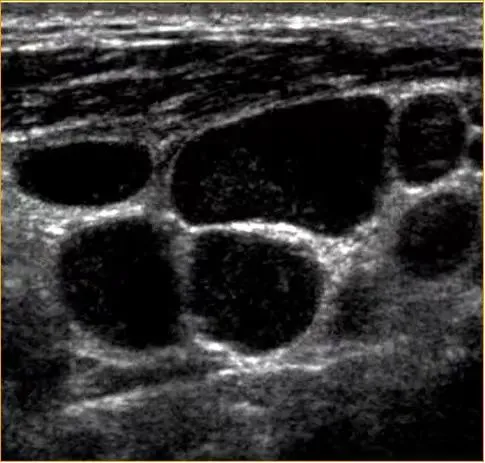

病例:左侧颈部无痛性结节2周,体检颈部可触及数个结节,可活动,无触痛。

超声描述:左侧颈部见数个肿大淋巴结,呈椭圆形,淋巴结之间无融合,大者约28x12mm,皮质增厚,髓质偏移,内部血流信号增多,呈树杈状分布。